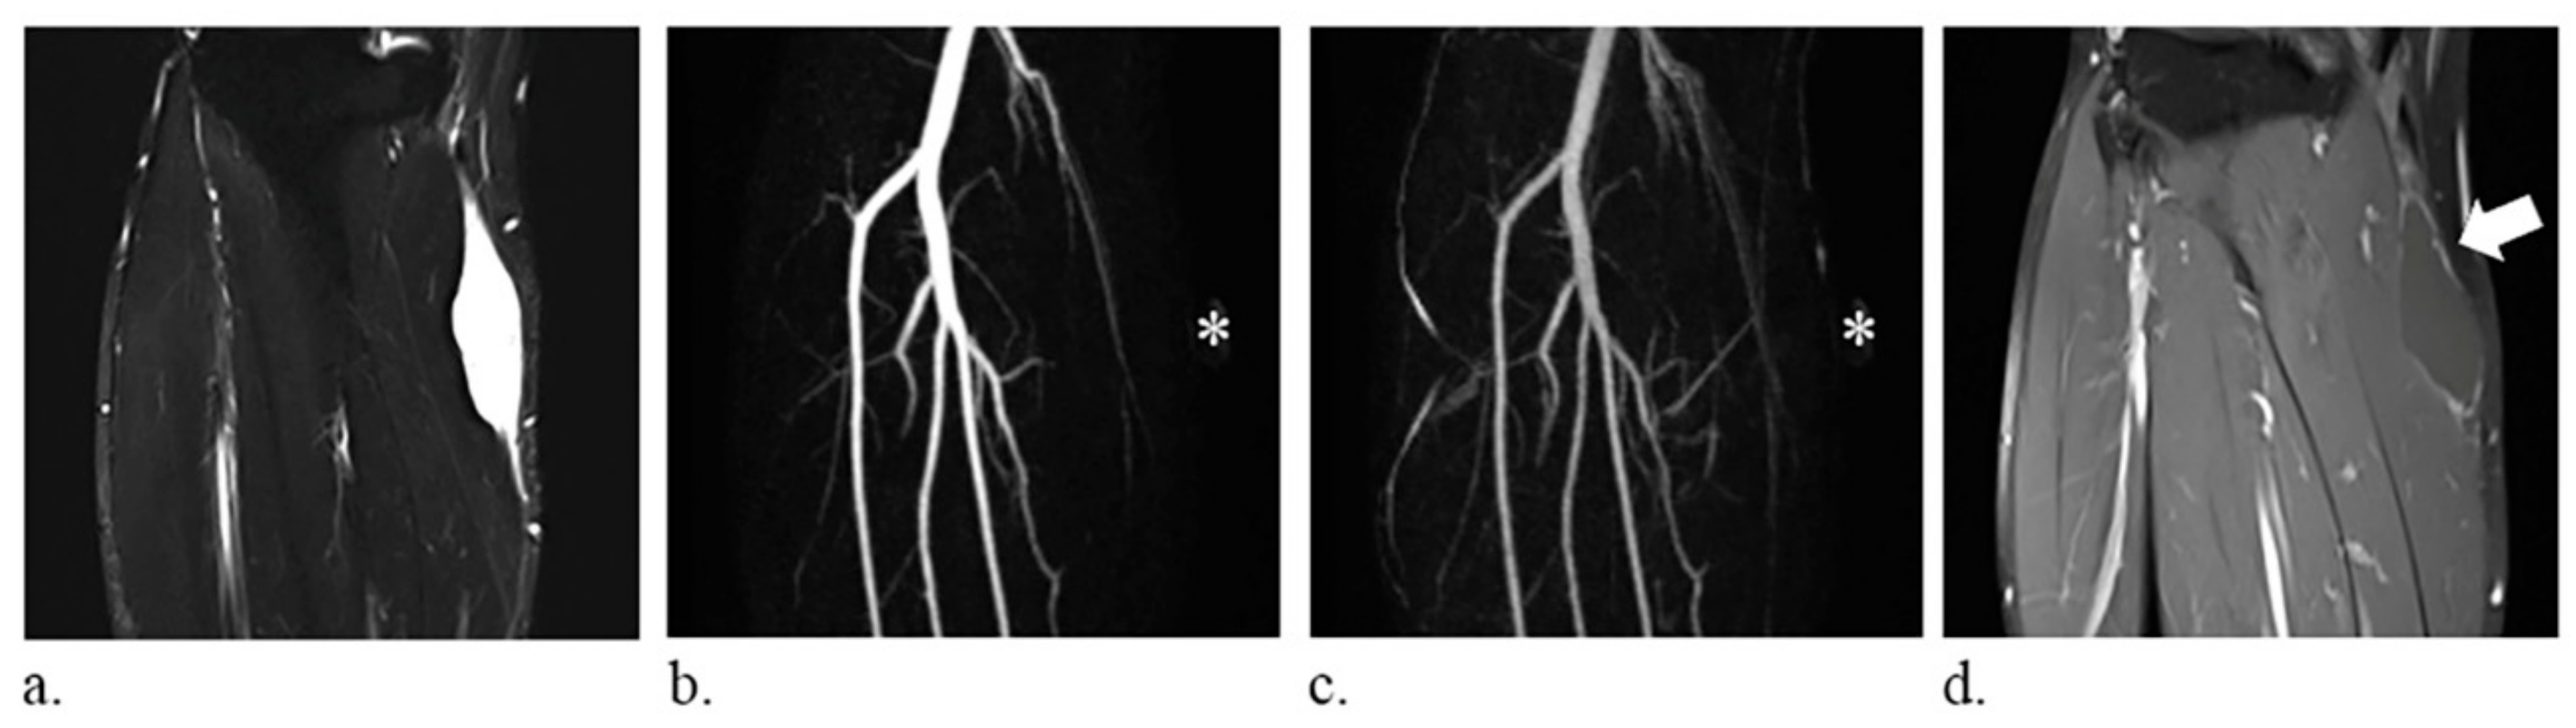

Figure 3.

A 59-year-old man with a synovial cyst of the right leg. (a) fat-suppressed T2-weighted coronal images (repetition time/echo time, 6780/74 ms) show a homogeneously hyperintense mass. (b–c) the lesion, indicated with an *, is not discernible on the coronal images of time-resolved magnetic resonance angiography and therefore defined as occult lesion. (d) static-enhanced T1-weighted coronal images (500/9.1 ms) with fat suppression reveal absence of internal enhancement of the lesion (arrow).